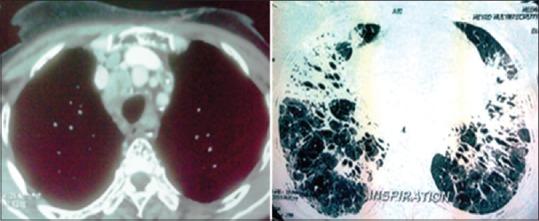

Literature on concurrent association of sarcoidosis with lymphoproliferative malignancies other than lymphoma e.g. multiple myeloma is meager. The rarity of the situation prompted us to report this patient who was a 51-year-old woman with a 2-years history of breathlessness, cough with expectoration, chest pain and backache. Initial evaluation revealed mild anemia, increased alkaline phosphatase with chest skiagram showing both lower zone non homogenous opacities with calcified hilar lymph nodes. CECT chest showed mediastinal with bilateral hilar lymphadenopathy, parenchymal fibrosis, traction bronchiectasis, ground glass opacities, septal and peribronchovascular thickening affecting mid and lower lung zones bilaterally. MRI Dorsolumbar spine was suggestive of marrow infiltrative disorder. EBUS FNA of intrathoracic nodes, EBB and TBLB confirmed sarcoidosis. PET CT revealed hyper metabolic activity in lung, multiple lymph nodes and lytic bone lesions. Serum protein electrophoresis and immunofixation revealed a monoclonal paraprotein, immunoglobulin IgG kappa type. Bone marrow biopsy revealed an increase in plasma cells (15%), but no granulomas. Diagnosis of Indolent or multiple myeloma with sarcoidosis was established. 12 cases of sarcoidosis and multiple myeloma have been reported in literature, and mostly preceding the onset of multiple myeloma by many years, in our case both were diagnosed concurrently.

关于结节病与淋巴瘤以外的淋巴增殖性恶性肿瘤(如多发性骨髓瘤)并发的文献很少。这种情况的罕见性促使我们报告这位51岁的女性患者,她有2年的呼吸困难、咳痰咳嗽、胸痛和背痛病史。初步评估显示轻度贫血,碱性磷酸酶升高,胸部X光片显示双下肺野不均匀阴影伴肺门淋巴结钙化。胸部增强CT显示纵隔及双侧肺门淋巴结肿大、实质纤维化、牵拉性支气管扩张、磨玻璃影、小叶间隔及支气管血管周围增厚,双侧中、下肺野均受累。胸腰椎MRI提示骨髓浸润性疾病。经支气管超声引导下经胸内淋巴结细针穿刺活检、支气管肺泡灌洗及经支气管肺活检确诊为结节病。PET-CT显示肺部、多个淋巴结及溶骨性骨病变有高代谢活性。血清蛋白电泳和免疫固定电泳显示单克隆副蛋白,免疫球蛋白IgG κ型。骨髓活检显示浆细胞增多(15%),但无肉芽肿。确诊为惰性或多发性骨髓瘤合并结节病。文献报道了12例结节病合并多发性骨髓瘤的病例,大多数情况下多发性骨髓瘤在多年前就已发病,而在我们的病例中两者是同时诊断的。